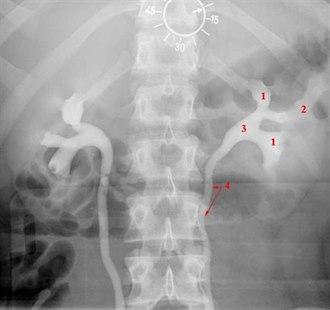

En normal urografi viser normal størrelse, form og posisjon av nyrer, urinledere og urinblære. Dersom nyrefunksjonen er normal, skal kontrastoppladning i nyrene synes på røntgen 2-5 min etter kontrastinjeksjonen. Etter 5-7 min skal nyrebekkenet være synlig. Senere bilder viser urinlederne og urinblæren som uttrykk for at kontrastvæsken passerer ned i de nedre urinveier. Etter urintømning skal det ikke være urin igjen i blæren.

Oversiktsbildet kan vise forkalkninger, f.eks. nyrestein. Etter kontrastinnsprøytingen gransker røntgenlegen om nyrene er i normal posisjon, om nyrekonturene er normale, om nyrene er normalt store, om nyren og nyrebekkenet ser normale ut, om urinlederne har normal størrelse eller om det er tegn til tilstopping og tilslutt om urinblæren ser normal ut.

De vanligste unormale funn er endringer i størrelse, form og posisjon til nyrene, nyrebekkenet og urinlederne. Tilstopping i urinveiene skyldes i de aller fleste tilfeller nyrestein, sjeldnere en svulst som har vokst inn i urinlederen. Funn av nyrecyster (cyste er et væskefylt hulrom) er et hyppig funn og er som regel uten betydning, men kan være vanskelig å skille fra svulster på urografi. Svulster kan gi en utbukning på nyrekonturen, eventuelt en forskyvning av strukturer inne i nyren, eventuelt økt nyrestørrelse - særlig hvis oppfylningen ligger ved den ene nyrepolen. Et slikt funn vil bli utredet videre med ultralyd eller CT. Forøvrig er det mulig å påvise en lang rekke mer eller mindre sjeldne tilstander ved urografi, men det vil føre for langt å beskrive disse her.